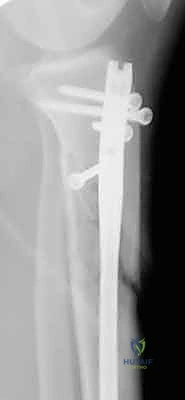

- التثبيت التشابكي (Interlocking): يتم تمرير مسامير صغيرة عرضية عبر العظم والمسمار النخاعي في الطرفين العلوي والسفلي، مما يمنع دوران العظم حول المسمار ويحافظ على طول الساق الطبيعي بدقة متناهية.

4. إدخال المسمار النخاعي والتثبيت النهائي

يتم تمرير مسمار التيتانيوم بدقة داخل العظم. وبمجرد التأكد من موضعه المثالي بالأشعة، يقوم البروفيسور هطيف بإدخال المسامير التشابكية (Locking Screws) العرضية في أعلى وأسفل المسمار لضمان التثبيت المطلق.

- تحميل الوزن: بناءً على استقرار الكسر، قد يسمح الدكتور هطيف بـ "التحميل الجزئي للوزن" (Partial Weight-Bearing) باستخدام العكازات. المسمار النخاعي قوي بما يكفي لدعم العظم أثناء المشي.